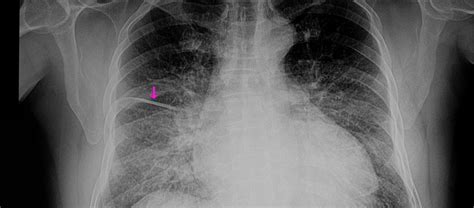

When a patient presents to the emergency department with acute respiratory distress, rapid diagnostic imaging becomes a cornerstone of clinical decision-making. Among the various tools available to physicians, the Pulmonary Edema Cxr (chest X-ray) remains the most frequently ordered and clinically significant diagnostic exam. Understanding the classic radiographic patterns of pulmonary edema is essential for medical professionals, as this condition represents a life-threatening accumulation of fluid in the pulmonary interstitial and alveolar spaces, often secondary to congestive heart failure or other systemic pathologies.

The Pulmonary Edema Cxr is highly sensitive for identifying fluid overload, though it requires a keen eye to differentiate between cardiogenic and non-cardiogenic causes. Radiologists and clinicians look for specific markers that indicate increased capillary hydrostatic pressure or altered vascular permeability. When evaluating a chest X-ray for this condition, the focus is placed on vascular prominence, redistribution of blood flow, and the presence of interstitial or alveolar opacities.

Key radiographic signs often appear in a specific sequence as the severity of the fluid overload progresses. Identifying these early can prevent the escalation to severe respiratory failure. The hallmark appearance is often referred to as "pulmonary congestion," which describes the initial phase of fluid accumulation.

• Cephalization: The redistribution of pulmonary blood flow to the upper lobes, which is one of the earliest signs of increased pulmonary venous pressure.

• Kerley B Lines: These are short, horizontal lines perpendicular to the pleural surface at the lung bases, representing thickened interlobular septa due to interstitial edema.

• Peribronchial Cuffing: This appears as a thickening of the bronchial walls, giving them a "donut" or "cuff-like" appearance on cross-section.

• Pleural Effusions: Fluid collecting in the pleural space, often bilateral but potentially unilateral, commonly seen in congestive heart failure.

• Bat-wing Opacities: In more severe cases, bilateral central alveolar opacities sparing the periphery of the lungs, indicating profound alveolar flooding.